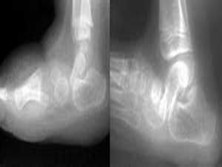

先天性垂直距骨

(畸形性距舟关节脱位、先天性凸形外翻足)

X线平片